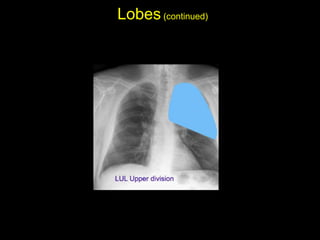

The document discusses the anatomy of the chest x-ray and CT scan by describing the lobes of the lungs and their locations. It also mentions the heart, mediastinum, hilum, and ribs. Several axial, coronal, and sagittal CT images are included with labels pointing out structures like the trachea, bronchi, lobes of the lungs, and fissures. In summary, the document provides an overview of lung and chest anatomy as seen on x-rays and CT scans through text descriptions and labeled medical images.